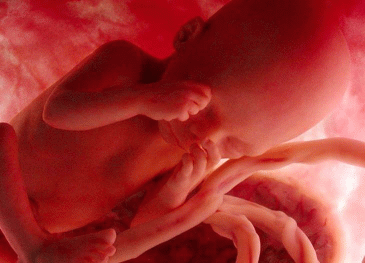

Il bambino ora prende quasi 200 grammi a settimana, pesa circa 1250 grammi e i suoi polmoni continuano ad esercitarsi nella respirazione. La testa cresce per fare spazio al cervello che ogni giorno vede nascere miliardi di nuovi neuroni, scalcia a più non posso ed è possibile contare i suoi movimenti per verificare il suo benessere e controllare che sia ben ossigenato. Per farlo, mettiti sdraiata su un fianco ogni giorno alla stessa ora, rilassati e concentrati su di lui, poi conta quanto tempo occorre al tuo piccolo per farsi sentire almeno dieci volte, conterai calci, pugni, singhiozzi e anche movimenti della testa e del sederino. La buona regola è che non servano più di due ore per arrivare a dieci.

Il bambino è arrivato a circa 1400 grammi, è più cicciottello e la sua pelle è più liscia e rosea.Con le sue continue capriole, potrebbe trovare la posizione definitiva per la nascita.

Ora il piccolo pesa circa 1600 grammi, ogni giorno che passa mette su il grasso sottocutaneo e la pelle è meno rugosa, lo spazio disponibile è poco e i suoi movimenti sono meno “tellurici”.

L’utero è arrivato a circa 12 centimetri sopra la linea ombelicale trasversa e il piccolo pesa circa 1800 grammi ed è lungo circa 40 centimetri.

La peluria che lo ricopre comincia a scomparire mentre la vernice caseosa lo ricopre totalmente. Gli occhi distinguono la luce dal buio e, soprattutto, distingue il caldo dal freddo, al punto tale che si muove se viene posta una fonte di calore vicino alla pancia.